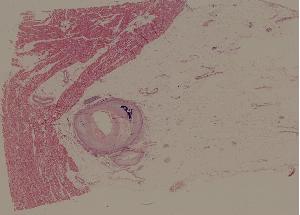

44.肾动脉硬化